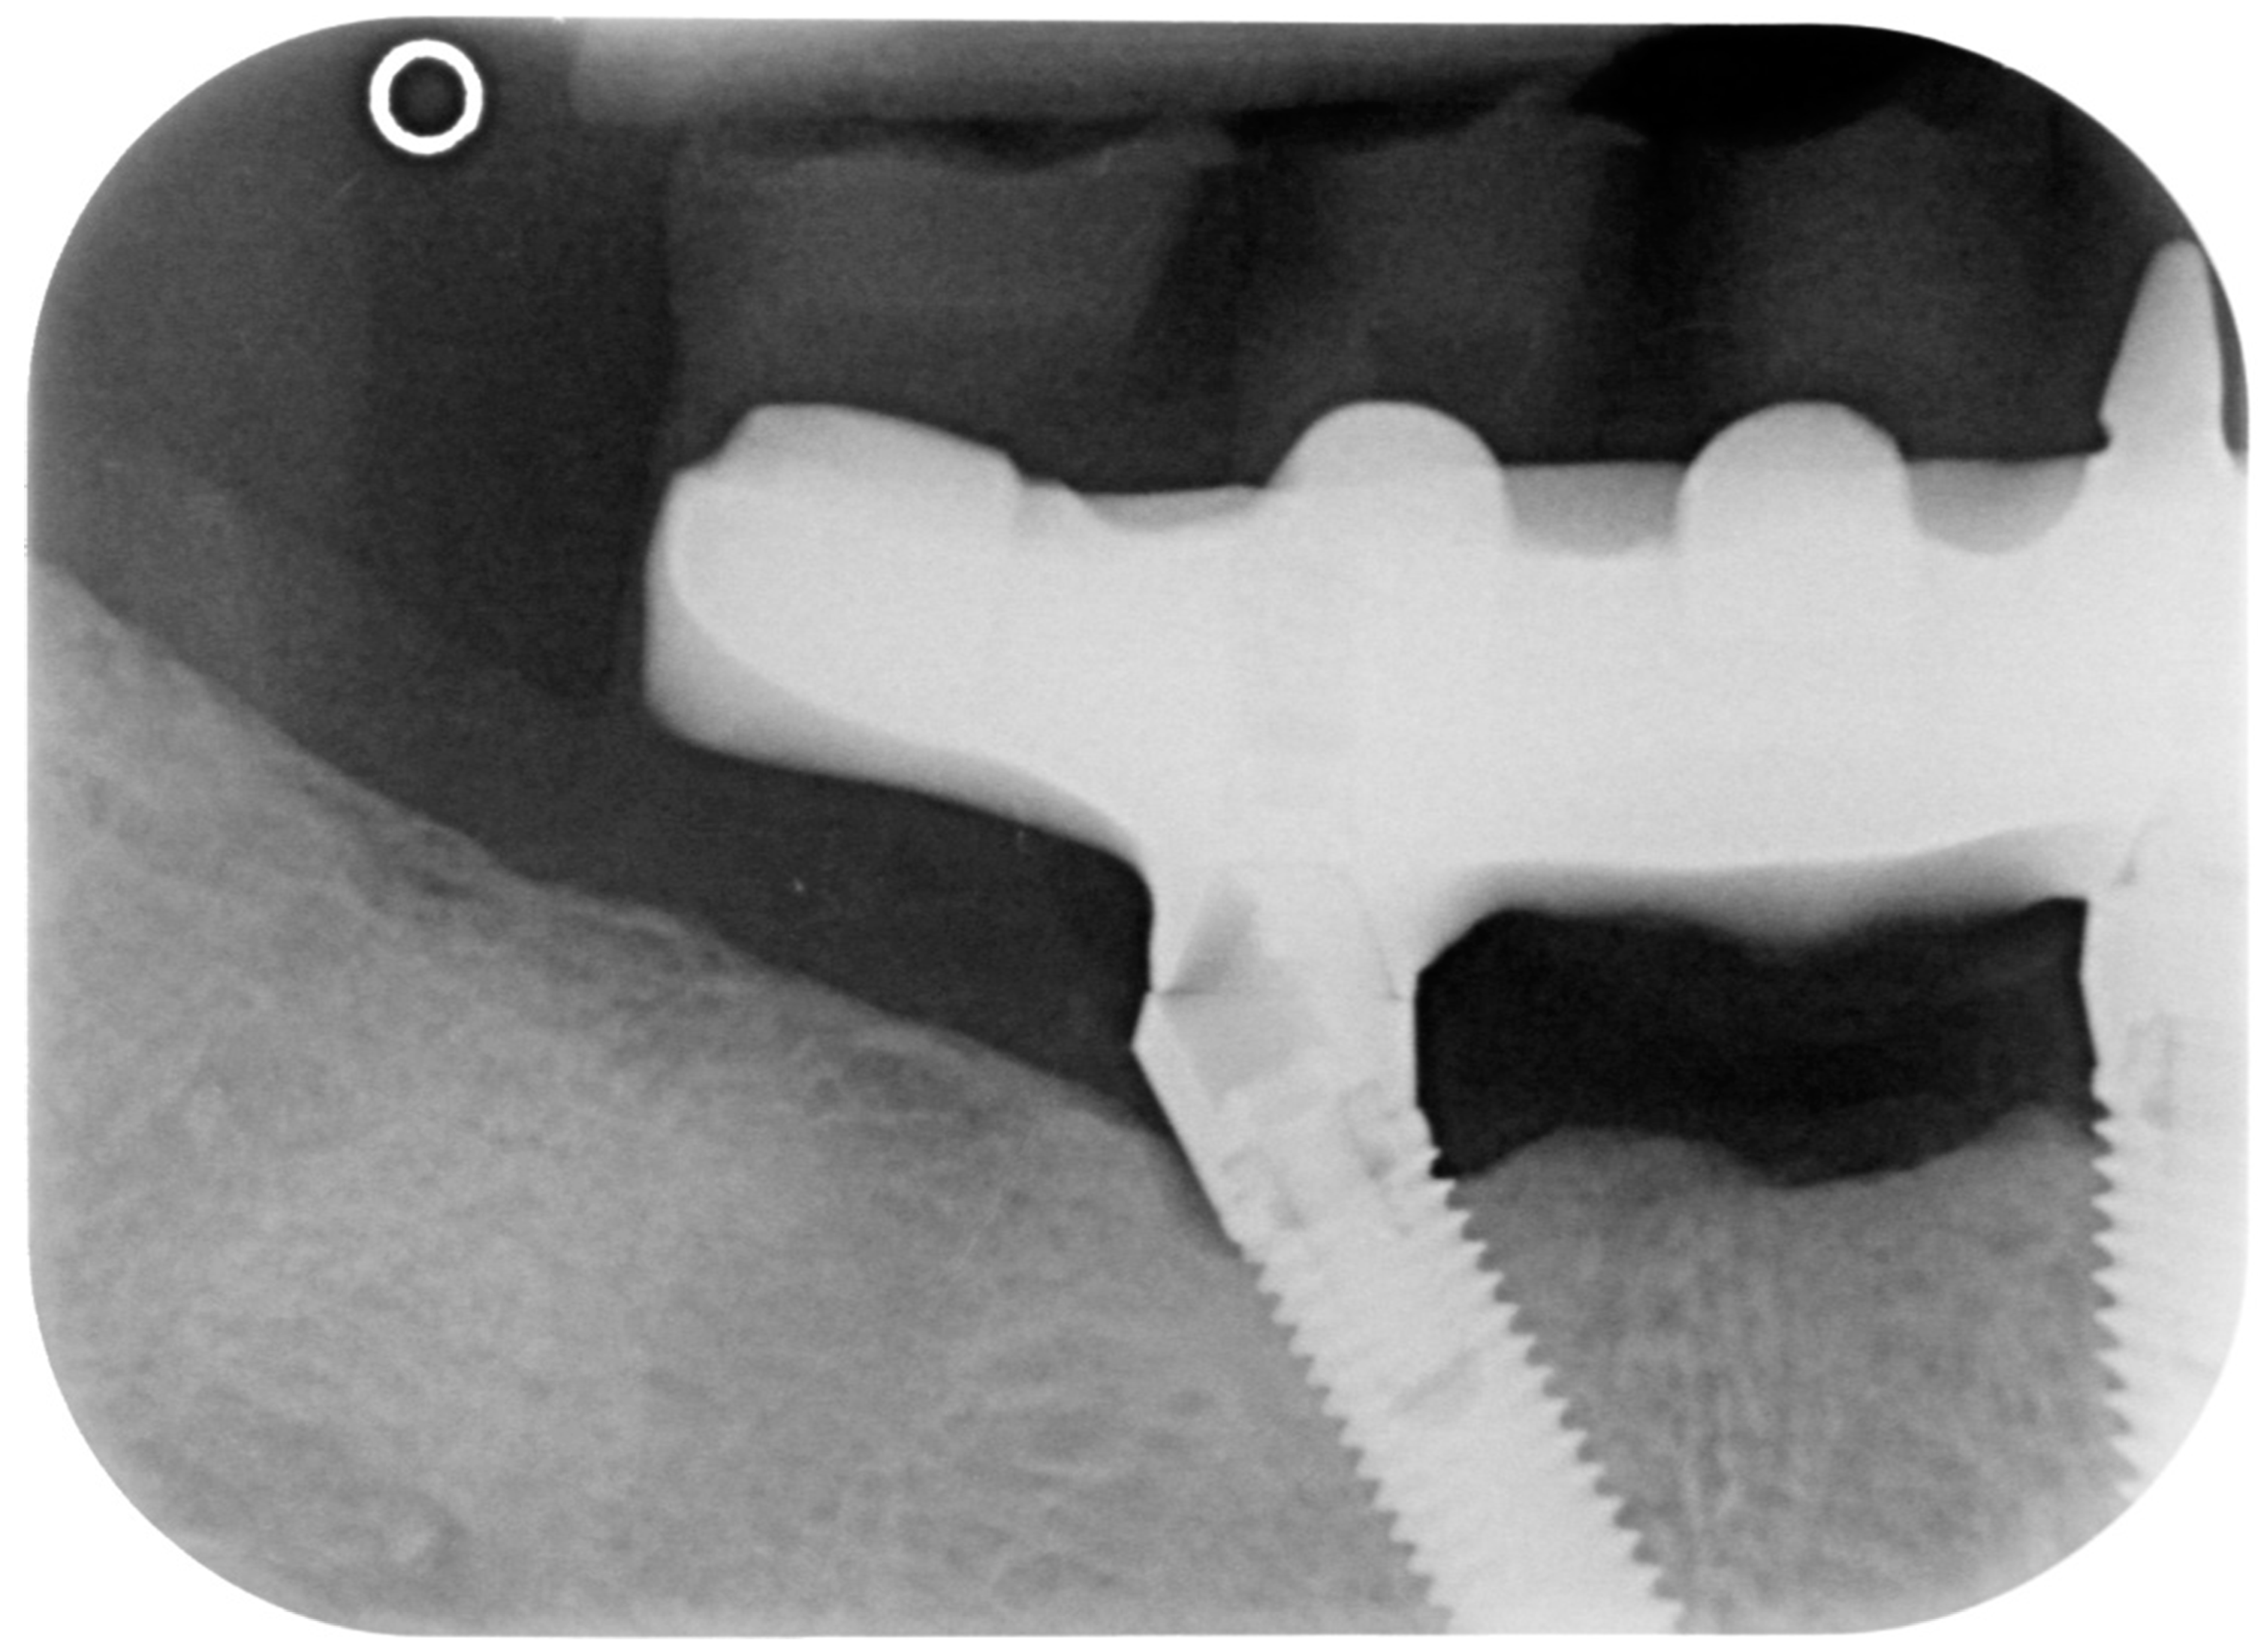

Figure 10.

X-ray of 3.5 dental implant in patient before treatment.

A bidimensional radiographic assessment of the lower jaw and upper jaw implants (with periapical and panoramic radiograph) was done. In the lower jaw implants, a concave bone resorption can be observed of about 4 mm mesial and distal to both distal implants (3.5 and 4.5). No bone resorption was revealed on the two lower jaw central implants and on the four implants positioned in the upper jaw.